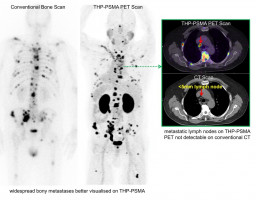

Data from this trial demonstrates that 68Ga-THP-PSMA is comparable with standard of care, with background physiologic uptake was significantly lower with 68Ga-THP-PSMA compared to 68Ga-HBED-PSMA, whilst not changing the management in these patients, as well as concordance in the number of metastases identified.

Group B observed patients with metastatic prostate cancer (represented by demonstration of at least one unequivocal PSMA-avid focus), and compared 68Ga-THP-PSMA PET/CT with standard of care, 68Ga-HBED-PSMA-11 PET/CT.

Uptake seen in the prostate on 68Ga-THP-PSMA PET/CT correlated with histopathologic PSMA expression seen on pathology finding following prostatectomy, highlighting the ability to non-invasively image prostate cancer directly.